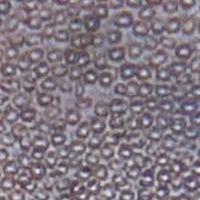

RBC Platelet segmentation Computer Vision Project

Medical Diagnostics: The "RBC Platelet Segmentation" model could be used by medical professionals in diagnosing conditions related to blood cells such as anemia, leukemia, or clotting disorders. By identifying and quantifying different cell classes, the model can aid in speeding up diagnosis and monitoring disease progress.

Pharmaceutical Research: In drug discovery and research, the model could be used to analyze changes in blood cells after drug treatment. Monitoring changes in RBC and platelet counts can provide insights into a medicine's efficacy and side-effects.

Blood Donation Centers: The model could be implemented at blood banks and transfusion centers to screen donated blood for any abnormalities in RBC and platelet levels, improving safety.

Veterinary Medicine: Similar to human medicine, this model could be used in examining blood samples of animals for diagnostics, treatment monitoring, and research purposes.

Education and Training: The model can be used in academic settings for teaching students about blood cell morphology and pathologies, making the learning process more interactive and practical. Image datasets of different cell classes can improve their understanding of microscopic anatomy and physiology.